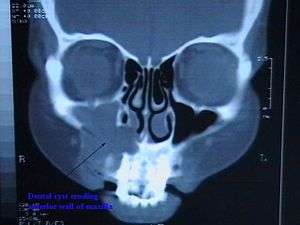

| CT scan through head showing a right periapical cyst | |

The periapical cyst (also termed radicular cyst, and to a lesser extent dental cyst) is the most common cyst of the jaw. It is caused by pulpal necrosis secondary to dental caries or trauma. The cyst lining is derived from the cell rests of Malassez. Usually, the periapical cyst is asymptomatic, but a secondary infection can cause pain. On radiographs, it appears a radiolucency (dark area) around the apex of a tooth's root.

Radiographically, Radicular Cysts are round or ovoid radiolucent areas surrounded by a narrow radio-opaque margin, which extends from Lamina Dura of involved tooth. In infected or rapidly enlarging cysts, radio-opaque margins may not be seen. Root resorption is rare but may occur.